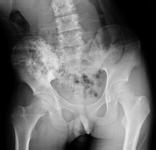

骨肿瘤是发生于骨骼或其附属组织的肿瘤,是常见病。同身体其它组织一样,其确切病因不明;骨肿瘤有良性,恶性之分,良性骨肿瘤易根治,预后良好,恶性骨肿瘤发展迅速,预后不佳,死亡率高。